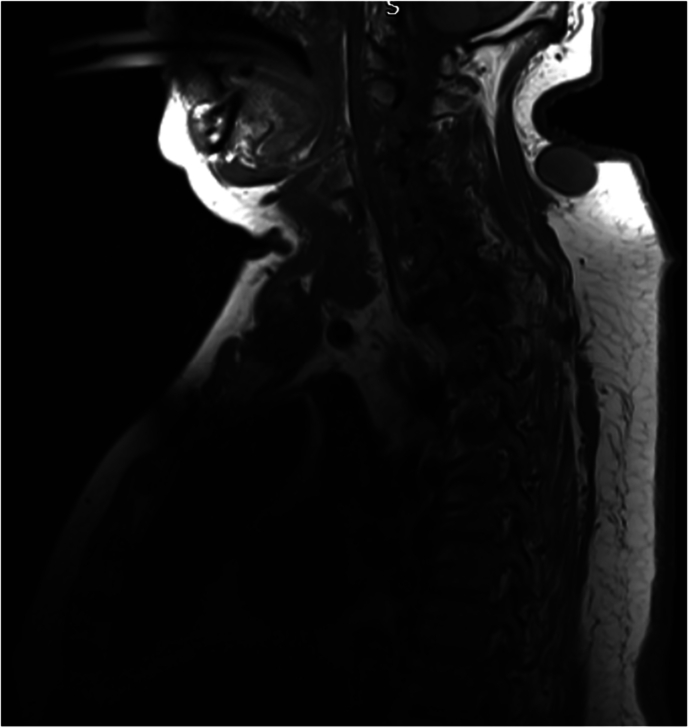

研究设计:回顾性分析6例Charcot脊柱关节病。目的:评价Charcot关节病的病因、临床表现(如疼痛、躯干不稳、自主神经反射障碍、痉挛)、症状发作前潜伏期、脊柱受累区及治疗策略。地点:英国国家脊髓损伤中心。方法:对6例确诊为Charcot型脊柱关节病的患者进行资料收集和分析。检查的变量包括病因、临床表现、受影响的脊柱区域、潜伏期和治疗方法的结果。对保守治疗和手术干预策略进行了评价。结果:患者均表现为疼痛、躯干失去控制、自主神经反射障碍、痉挛等常见临床表现,症状发作前潜伏期不同。胸椎是最常见的受累部位。在大多数病例中,保守治疗成功地稳定了症状,而在严重的躯干不稳定、难治性疼痛或影响活动的畸形的情况下,手术干预是必要的。结论:保守治疗应是沙尔科关节病的首选治疗方法。手术干预保留给有重大临床进展的病例,如未解决的疼痛,躯干畸形导致的活动受限,或脊柱病理引起的紧急并发症。

Results: Patients exhibited common clinical manifestations such as pain, loss of trunk control, autonomic dysreflexia, and spasticity, with varying latency periods before symptom onset. The thoracic spine was the most frequently affected region. Conservative management successfully stabilized symptoms in most cases, while surgical intervention was necessary in instances of severe trunk instability, refractory pain, or deformity impacting mobility.